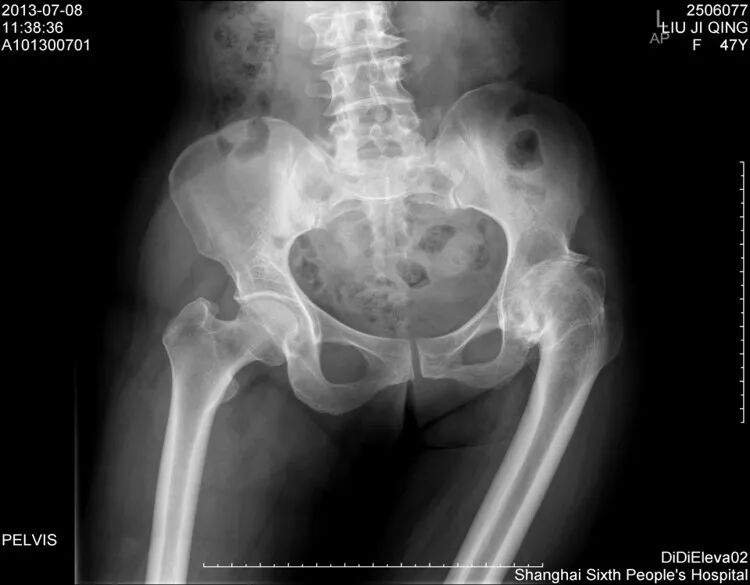

先看病例!

女性患者,48岁,右髋疼痛25年,加重1年